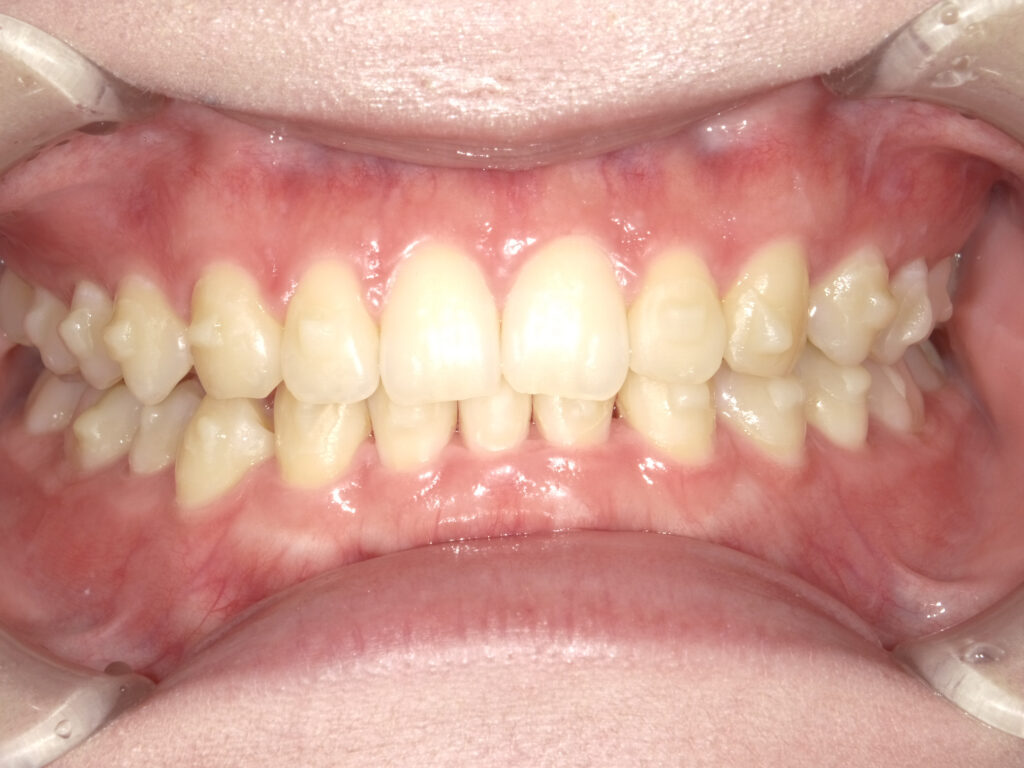

正面

治療後